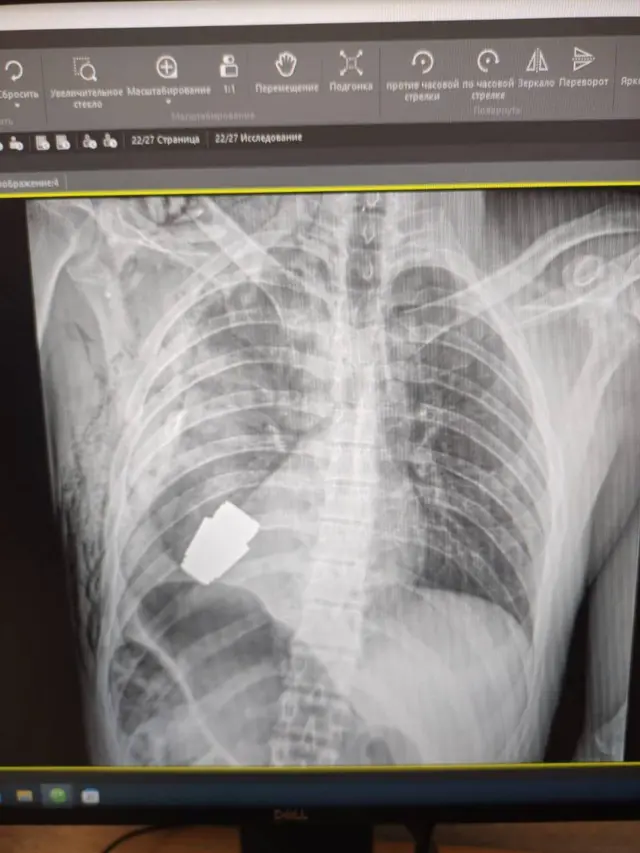

Лікарі провели операцію з видалення гранати ВОГ, яка не розірвалася, з тіла військовослужбовця.

Осколковий боєприпас калібру 40-мм використовують для підствольних гранатометів та для ручних гранатометів. Вага гранати складає близько 275 грамів.

Як розповіла Ганна Маляр, операцію проводив військовий хірург Андрій Верба. Видалення проводили без електрокоагуляції, оскільки граната могла здетонувати у будь-який момент.